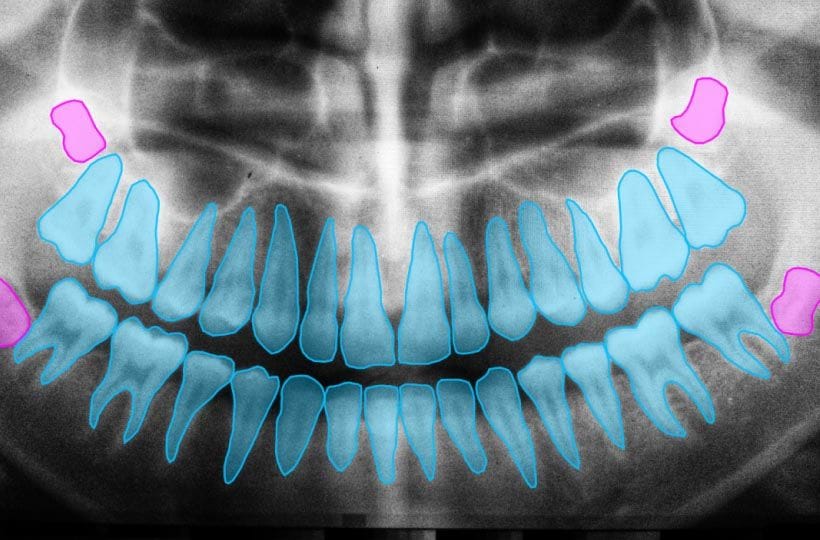

Одне із застосувань штучного інтелекту – радіологія. Ця технологія може аналізувати складні медичні зображення, як-от рентгенівські промені, КТ та МРТ, швидше, ніж експерт-людина. Це дозволяє лікарям швидше визначати потенційні ризики для здоров’я та покращує їхню здатність планувати відповідне лікування для своїх пацієнтів.

ШІ в медичній візуалізації та аналізі

Одним із найбільш перспективних застосувань штучного інтелекту (ШІ) в охороні здоров’я є медична візуалізація та аналіз. Завдяки комп’ютеризованим алгоритмам штучний інтелект може розбивати складні дані зображень і аналізувати їх для цілого ряду діагностичних цілей. Це має численні переваги як для пацієнтів, так і для медичних працівників, включаючи швидшу діагностику, більш точні показники та покращення результатів лікування.

Домінування програмного забезпечення в рамках штучного інтелекту на ринку охорони здоров’я також відображається в його використанні для медичної візуалізації. Комп’ютери на базі штучного інтелекту можуть швидко обробляти великі обсяги даних, виявляючи тонкі закономірності або зміни, які людське око може не помітити. Наприклад, штучний інтелект може визначати потовщення в конкретних м’язових структурах або відстежувати зміни кровотоку, які можуть вказувати на певні захворювання. Крім того, він виявився корисним для виявлення ракових уражень, а також моніторингу неврологічних захворювань і торакальних ускладнень.

Завдяки штучному інтелекту постійно вдосконалюються медичні візуалізації, наприклад моделі машинного навчання для виявлення захворювань очей, спричинених діабетом, із таким же рівнем точності, як і люди. Ці кроки мали значний вплив на галузь: очікуваний дохід зросте з 753,9 мільйонів доларів США у 2022 році до 14 мільярдів доларів США до 2028 року зі швидкістю 34,8%.